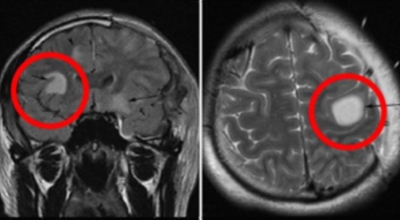

뇌출혈은 발작 직후 안정을 취해야 해요. 뇌부기를 가라앉히기 위해 약물 요법으로 고농도 포도당, 덱사메타존, 만니톨 등을 투약할 수 있고 뇌의 혈액 순환을 회복시키는 주사와 지혈제, 진정제 등을 활용할 수 있답니다. 혈종의 크기가 중등도 이상으로 마비 증세가 있다면 머리뼈에 작은 구멍을 내서 관을 넣어 혈종을 뽑아내는 수술을 시행할 수 있습니다.

혈압성 뇌출혈인 경우 혈종의 크기가 작으며 환자의 증상이 경미하면 약물 치료를 시행해요. 혈종의 크기가 아주 크며 뇌가 심하게 부어오를 때는 응급으로 머리뼈를 절개해 혈종을 빠르게 제거해야해요. 응급조치가 늦어지면 뇌압이 상승해 의식을 잃고 사망에 이를 수 있기 때문인데요 이렇게 증상이 심할 때는 수술이 잘 되었더라도 예후가 좋지 못할 때가 많다고 해요.